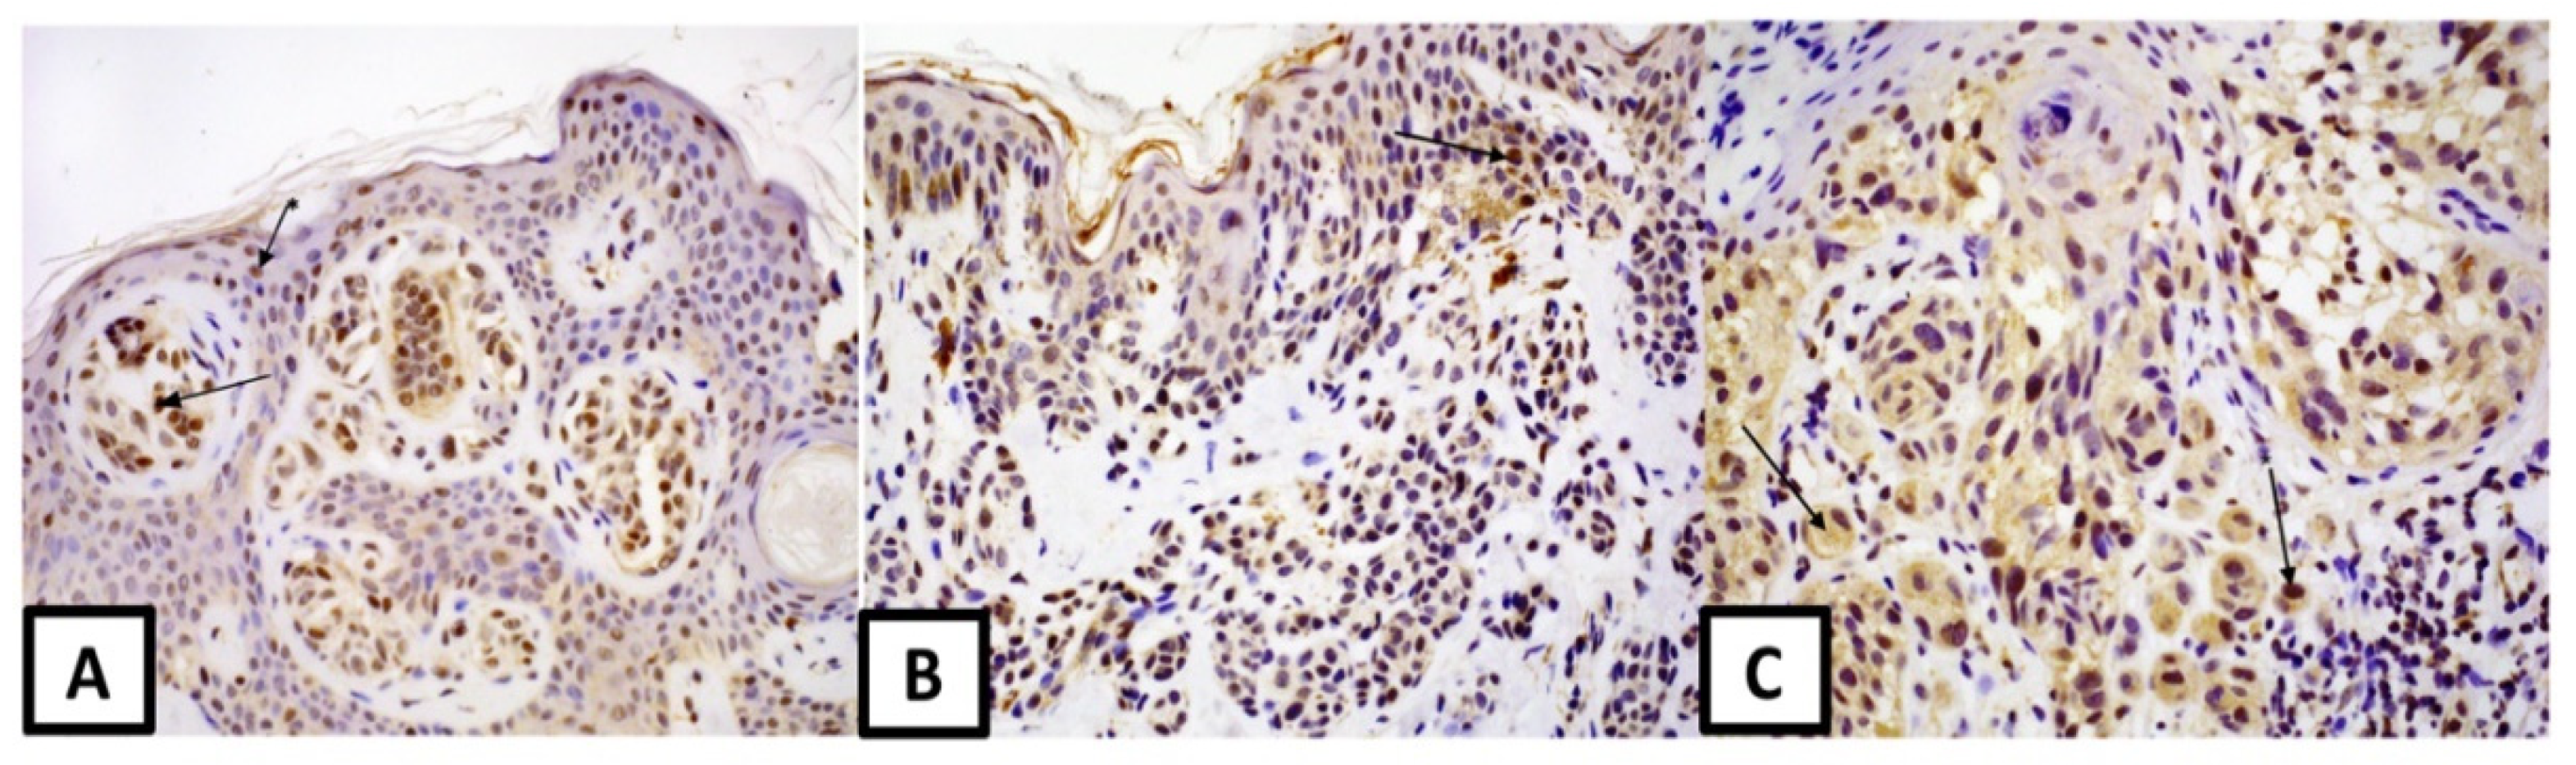

3. Results